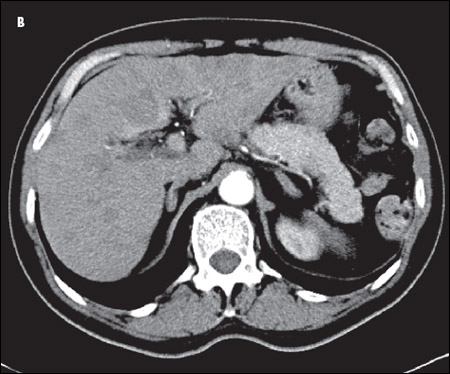

A CT scan of the chest showed an amorphous soft tissue mass that encased and constricted the right main pulmonary artery and the right main stem bronchus (A). Extensive round masses were visible in the liver; the largest mass was in the right medial hepatic lobe and measured 2.7 × 2.4 cm (B).

An extensive evaluation of the patient's mass lesions and cytopenias was initiated. He was HIV-positive, but results of tests for hepatitis B and C were negative. Liver function tests revealed the following levels: albumin, 3.1 g/dL; total protein, 5.8 g/dL; direct bilirubin, 0.3 mg/dL; total bilirubin, 1.0 mg/dL; alkaline phosphatase, 175 U/L; alanine aminotransferase, 156 U/L; and aspartate aminotransferase, 92 U/L. Haptoglobin level was 27 mg/dL, and lactate dehydrogenase level was elevated at 1168 U/L. The fibrinogen level was normal at 274 mg/dL, but the D-dimer level was elevated at 602 ng/mL. Results of an enzyme-linked immunosorbent assay for heparin(-induced platelet antibodies were negative. A review of the peripheral smear (C) showed no platelet clumping, schistocytes, or immature cells. Blood and urine cultures showed no bacterial or fungal growth.

SCLC typically presents as a large central mass (as in this patient) with mediastinal adenopathy. SCLC can infiltrate the submucosa, causing either intrinsic or extrinsic compression of the bronchi. SCLC has a propensity for spreading to the liver, brain, bone, and bone marrow. The neutropenia and thrombocytopenia seen in this man can be explained by the infiltration of his bone marrow by the SCLC. In a series of 129 patients with SCLC, 30% had bone marrow involvement. However, in only 2.3% was the bone marrow the only site of metastatic disease.7 Other presenting symptoms include cough, dyspnea, hemoptysis, chest pain, postobstructive pneumonia, and the paraneoplastic syndromes mentioned above.